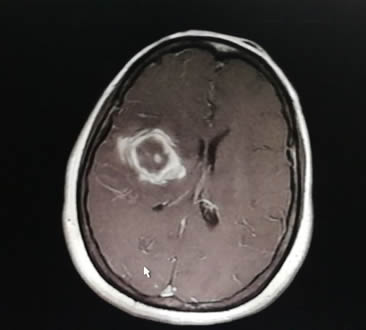

50岁的林女士因突发头疼,左侧肢体无力,无法行动,经MRI检查显示,其脑深部病变,合并出血,医生诊断为右侧基底节区巨大海绵状血管瘤破裂出血。据主管医生江常震副主任医师介绍,此类肿瘤位置越深,手术难度越大,林女士的血管瘤直径3.5cm,且脑部病变位置深,位于皮层功能区深部,难以准确暴露,且周围有重要的神经纤维束(皮质脊髓束)紧贴瘤壁穿行,使得手术难度加大,虽然显微镜下手术已有开展,但稍有不慎,便有造成永久性瘫痪或偏瘫的风险。

考虑到林女士的年龄及身体情况,经过详细的术前病例讨论,我院神经外科专家康德智教授和林元相教授决定采用功能神经导航结合Endoport内镜切除血管瘤。Endoport内镜新技术是利用一个内径仅2cm的透明管道,通过在头皮切开一个直径为5cm的口,避开功能区皮层进入额叶深部,为内镜操作建立一个安全的手术通道。利用该内镜高清、多角度侧视的特点,容易分辨病变与组织界面,并在推移而非切断周围纤维束的情况下完成肿瘤切除。手术结束时再拔除Endoport,脑组织弹回并恢复其自然位置。

历时3小时,在康德智教授团队的努力下,血管瘤所在位置被准确定位并顺利切除。术后CT提示血管瘤完全切除,功能MRI复查深部神经纤维束均正常。目前患者左侧肢体肌力较术前明显改善,可下床行走,生活基本自理。